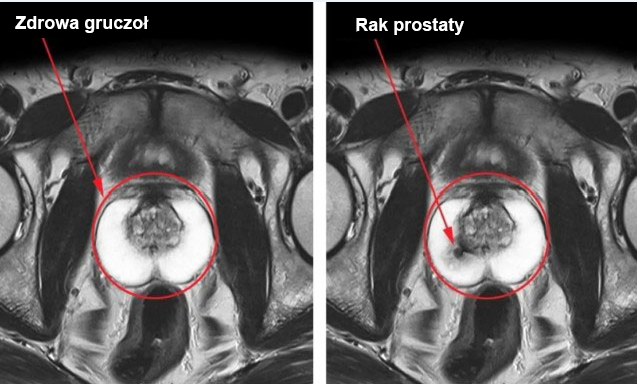

Problemy z prostatą: zapalenie gruczołu krokowego, przerost prostaty, a w niektórych przypadkach zwiększone ryzyko raka prostaty w ciągu 3-4 lat.

Chroni prostatę i zapobiega problemom z gruczołem krokowym

Większość problemów z prostatą u mężczyzn wiąże się z zastojem płynu nasiennego. Ponieważ Primal Orgin przywraca aktywne życie seksualne, pomaga również wyeliminować ten problem. Co więcej, jego formuła zawiera wiele aktywnych składników, które mają pozytywny wpływ na tkanki prostaty. Dlatego nie tylko wspiera potencję, ale także poprawia zdrowie prostaty i może zapobiegać powikłaniom, takim jak przerost prostaty.

Rak prostaty może rozwinąć się u mężczyzn z zaburzeniami erekcji w ciągu 8-12 lat. Najlepszym sposobem na zmniejszenie tego ryzyka jest utrzymanie aktywnego życia seksualnego do późnej starości, najlepiej nawet po 80 roku życia.